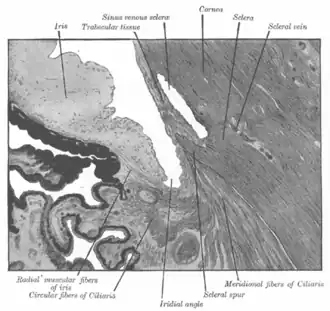

Enlarged general view of the iridial angle. (When enlarged, visible with older label of 'trabecular tissue') | |

The trabecular meshwork is an area of tissue in the eye located around the base of the cornea, near the ciliary body, and is responsible for draining the aqueous humor from the eye via the anterior chamber (the chamber on the front of the eye covered by the cornea).

The meshwork is divided up into three parts, with characteristically different ultrastructures:

- Inner uveal meshwork - Closest to the anterior chamber angle, contains thin cord-like trabeculae, orientated predominantly in a radial fashion, enclosing trabeculae spaces larger than the corneoscleral meshwork.

- Corneoscleral meshwork - Contains a large amount of elastin, arranged as a series of thin, flat, perforated sheets arranged in a laminar pattern; considered the ciliary muscle tendon.[2]

- Juxtacanalicular tissue (also known as the cribriform meshwork) - Lies immediately adjacent to Schlemm's canal, composed of connective tissue ground substance full of glycoaminoglycans and glycoproteins. This thin strip of tissue is covered by a monolayer of endothelial cells.